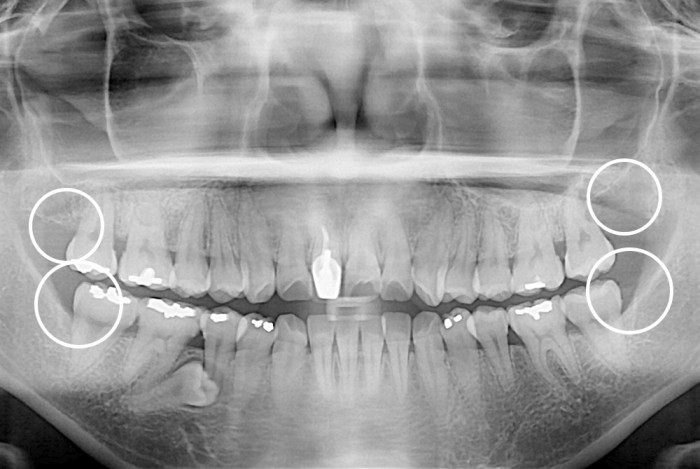

[사랑니] 사랑니

PX20160901_094424_0693_00000000.jpg

치료전 : 2016-09-01

세종치과는 구강악안면외과학 박사이신 원장님이 발치하는 치과입니다.